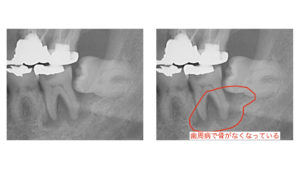

③手前の歯が歯周病になる

親知らずと手前の歯の隙間から歯周病菌が感染を起こすとその部分の骨が溶けてなくなることもよく起こります。

通常痛みなどの症状が出ることは少ないですが、痛みが出たときは手前の歯も巻き込んで2本抜歯となる場合があります。

手前の歯を支える骨が半分以上なくなっています。

手前の歯の骨はほとんどがなくなっています。親知らずだけではなく手前の歯も抜かないといけない状態です。